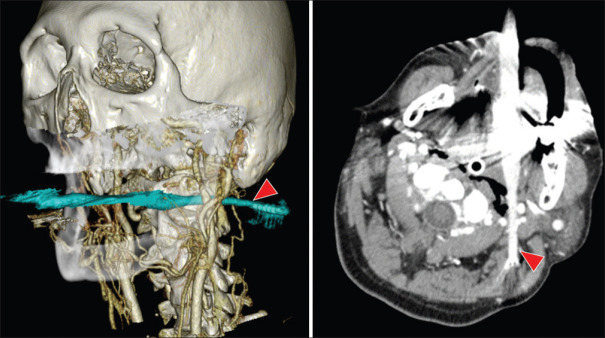

Most toothbrush-induced oral injuries occur in children and are relatively shallow, involving the oral mucous membranes and musculature, but rarely deeper layers. Here, the management of an adult case of pharyngeal injury caused by a toothbrush is discussed. A man fell while brushing his teeth, and his toothbrush stuck in his throat. Contrast-enhanced computed tomography showed a toothbrush stuck in the left parapharyngeal space, reaching the subcutaneous tissue of the posterior neck. The toothbrush was surgically removed because blind removal could damage major cervical arterioles and nerves. In intraoral injuries caused by deep penetrating toothbrushes, there is a risk that the injury extends to the major arterioles and nerves of the neck. The need for imaging studies, methods of removal, and possible complications should all be considered before taking an appropriate removal action.